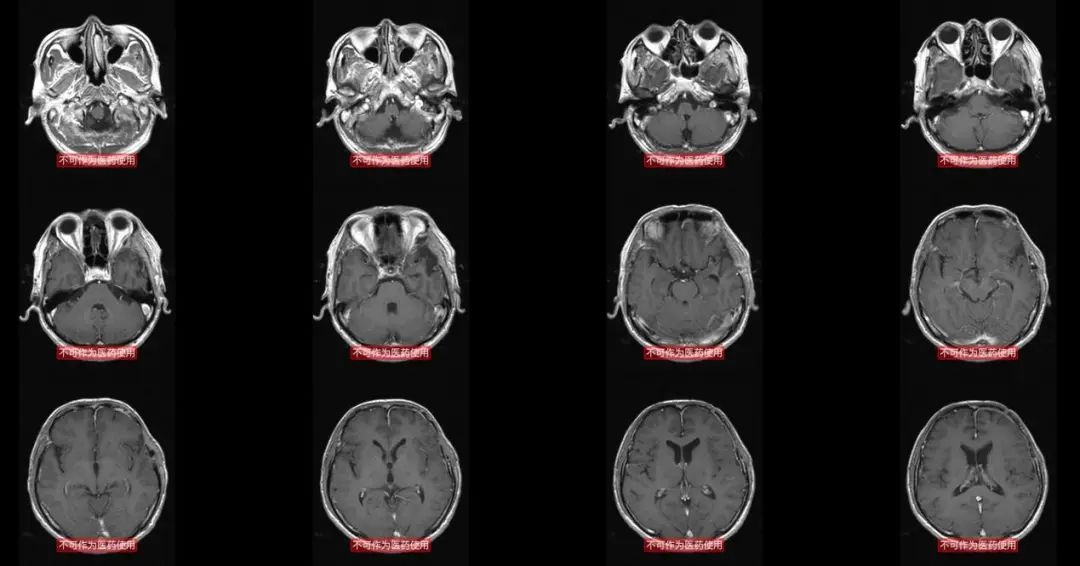

这是术前的磁共振,肿瘤与侧裂静脉的关系比较密切,需要关注。

这是12月21日复查的头颅MR,肿瘤没有复发征象,全切,也没有明显脑水肿。